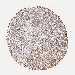

STOMACH CANCER - Protein expressioni

A mouse-over function shows sample information and annotation data. Click on an image to view it in a full screen mode. Samples can be filtered based on level of antibody staining by selecting one or several of the following categories: high, medium, low and not detected. The assay and annotation is described here.

Note that samples used for immunohistochemistry by the Human Protein Atlas do not correspond to samples in the TCGA dataset.

Antibody stainingi

Antibody staining in the annotated cell types in the current human tissue is reported as not detected, low, medium, or high, based on conventional immunohistochemistry profiling in selected tissues. This score is based on the combination of the staining intensity and fraction of stained cells.

Each image is clickable and will lead to virtual microscopy that enables deeper exploration of all samples and also displays staining intensity scores, fraction scores and subcellular localization as well as patient and tissue information for each sample.

Antibody HPA040820

Antibody CAB013089

Staining

High

Medium

Low

Not detected

Intensity

Strong

Moderate

Weak

Negative

Quantity

>75%

75%-25%

<25%

None

Location

Nuclear

Cytoplasmic/membranous

Cytoplasmic/membranous,nuclear

Adenocarcinoma, NOS